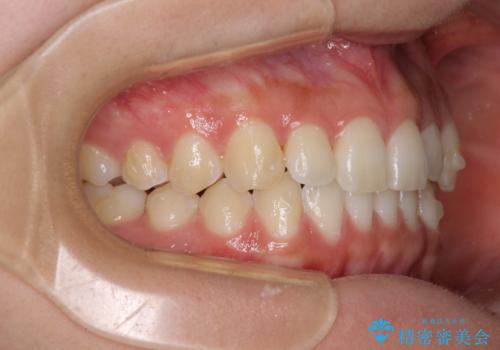

- 前歯の叢生と、奥歯の咬み合わせの悪さを気にして来院された患者様です。

左下には後続永久歯の欠損した乳歯が残存しており、叢生を相まって咬合関係が乱れていました。

乳歯は抜歯し、インビザラインにて矯正治療を行いながら、並行してインプラントによる補綴治療を行うこととしました。